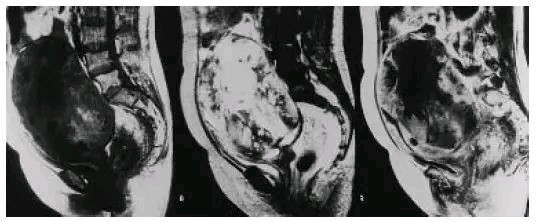

子宫肌瘤良性变的时候的增强延迟显像的MRI图像

子宫肉瘤的增强延迟显像的MRI图像